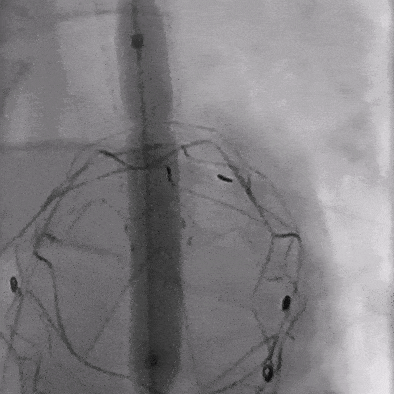

04. 沿左肱动脉引入5F Ver导管,头端垂直抵住主体支架覆膜,引入0.035″长泥鳅导丝配合导管顺利破膜,进入主动脉。

05. 0.035″长泥鳅导丝进一步超选进入降主动脉段,并沿右股动脉引入抓捕器抓取泥鳅导丝建立导丝路径,依次逐级使用4*40mm、6*40mm、8*40mm Amanda球囊扩张破膜处。期间可见明显受压切迹影。

06. 沿右股动脉引入8F长鞘,置入8*50mm Viabahn覆膜支架于开窗处,远端避开左椎动脉,近端超过覆膜支架1cm并完成释放。